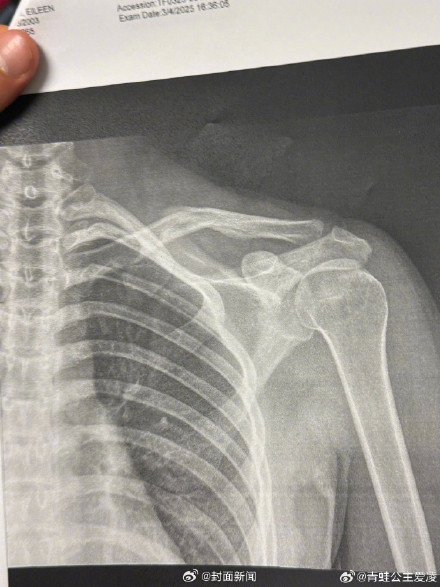

3月9日,爱凌发心碎表情并晒肩部X光片,显示锁骨受伤。日期是3月4日,目前尚不得知本次的伤病是新伤还是旧伤。上个月谷爱凌在训练中再次受伤,宣布不得不退出亚冬会。评论区网友纷纷留言:期待重回赛场,祝早日康复。